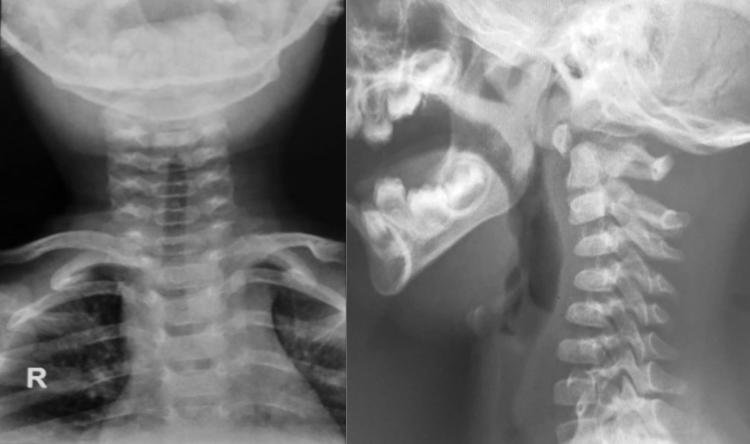

Radiografía de columna cervical frente y perfl

Se presenta un caso poco frecuente de espondilolisis cervical de C2, en un lactante de 1año y 7 meses de edad. Con el objetivo de mostrar las difcultades diagnósticas y terapéuticas, conociendo aquellos signos radiológicos que permiten identifcar esta infrecuente patología así como el algoritmo diagnóstico. Se optó por un tratamiento conservador con collarete, y se controló de forma regular obteniendo una muy buena evolución.